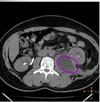

- What is shown in the following image?

- What are signs and symptoms a patient with this condition would present with?

- What test can help you identify?

A

- Psoas abscess

- Back or flank pain

- Fever

- Inguinal mass

- Limp (lower abdominal pain exacerbated by extending limb)

- Anorexia

- Weight loss

- Psoas sign would be positive

Side note: more common in populations with tuberculosis